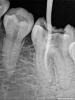

Денис481 Опубликовано 28 июля, 2012 Поделиться Опубликовано 28 июля, 2012 45 зуб протейперами обработал,на снимке перед пломбировкой(справа) все хорошо,а запломбировал чуть не дошел до апекса,как вы думаете грозит зубу что то или нет? просто переживаю как то только начинаю работать хочется чтоб все идеально было как в учебнике,хотя у меня есть во рту зуб который намного хуже пролечен там до апекса не дошли мм 2 но тфу тфу 2 года полет нормальный,а тут я померил 0.4 не дошел.....обидно что канал хороший а так получилось,кстати пломбировал ah+ c гуттой конусной под протейпер Ссылка на комментарий

Денис481 Опубликовано 28 июля, 2012 Автор Поделиться Опубликовано 28 июля, 2012 одним штифтом конусным силлер ah +,сначала наполнителем чуть по стенкам потом нанес на штифт и в канал,щас листал литературу там написано что надо не доходить до рентген верхушки при витальной экстерпации 1.5 мм и при девитальной 1мм так что выходит правильно все)))) Ссылка на комментарий

Afffinity Опубликовано 28 июля, 2012 Поделиться Опубликовано 28 июля, 2012 Методом одного штифта лучше не пломбировать, пролатералить куда лучше имхо. При методе одного штифта не достигается плотности паковки, а соответственно герметизма. Но для начала гуд Ссылка на комментарий

Magdalena Опубликовано 31 июля, 2012 Поделиться Опубликовано 31 июля, 2012 одним штифтом конусным силлер ah +Отчего не люблю конусные штифты... мне кажется, вводят в заблуждение начинающих докторов, особенно 06 конус.Год назад доктор первого года работы в нашей клинике полечилНичего так, в дистальном не дошел чуть-чуть, подумаешь Нашла снимки в процессе раз штифт два штифт и триПациент пришел на днях - все болит, жевать не могу. Открыла - в дистальном один конусный и параллельно ему ниточка пульпы в канале сидит такая Тут конечно, мех и мед обработка хромала, как так вот взять и засунуть гутту в пульпу?? А по снимку и руководство не придралось - 1,5 мм в витальных зубах допустимо, типа Перелечила: К3, гипохлорит, УЗ, временное пломбирование каласепт, гипохлорит, УЗ, ЭДТА. Пломбирование гутта 02 и АН + Ссылка на комментарий